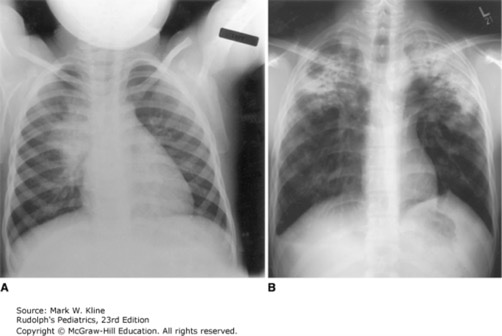

A: A chest radiograph from a child with early pulmonary tuberculosis demonstrating hilar adenopathy and perihilar infiltrate. B: An adolescent with severe bilateral upper lobe tuberculosis, with cavitation on the right side.

Source: Kline MW. Rudolph's Pediatrics, 23rd ed. New York, NY: McGraw-Hill Education; 2018.